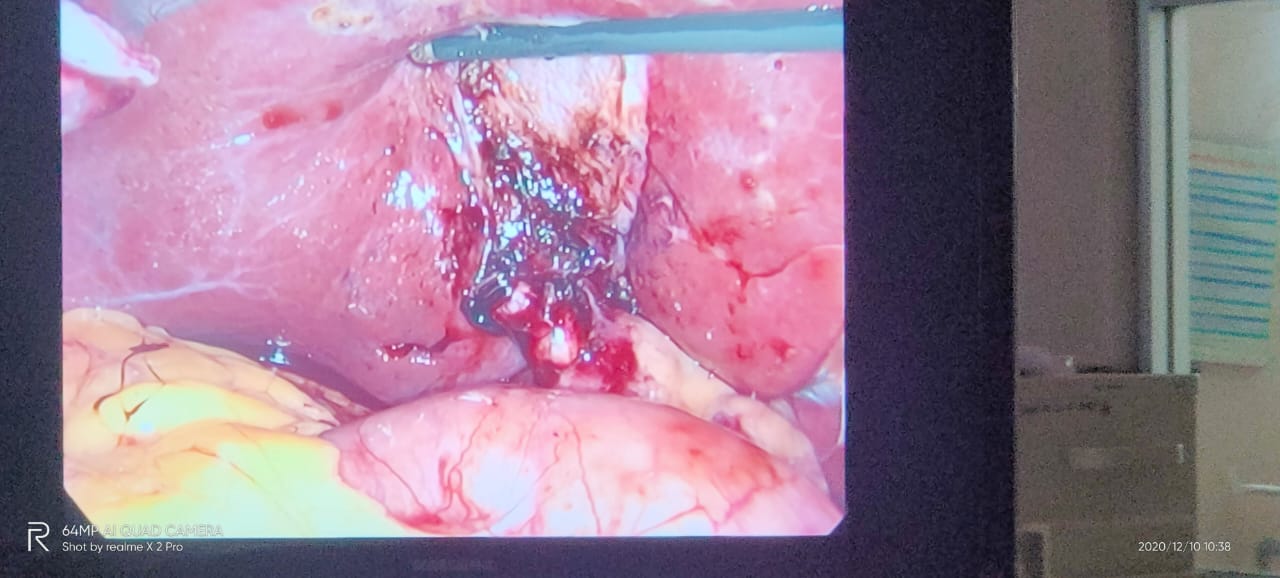

Multiple worms in CBD are well known, and ultrasound is considered a very useful modality for diagnosis and for follow-up. Also, there can be worms in bile ductules that may lead to the persistence of symptoms despite of CBD clearance. Follow-up ultrasound is thus mandatory if symptoms persist.